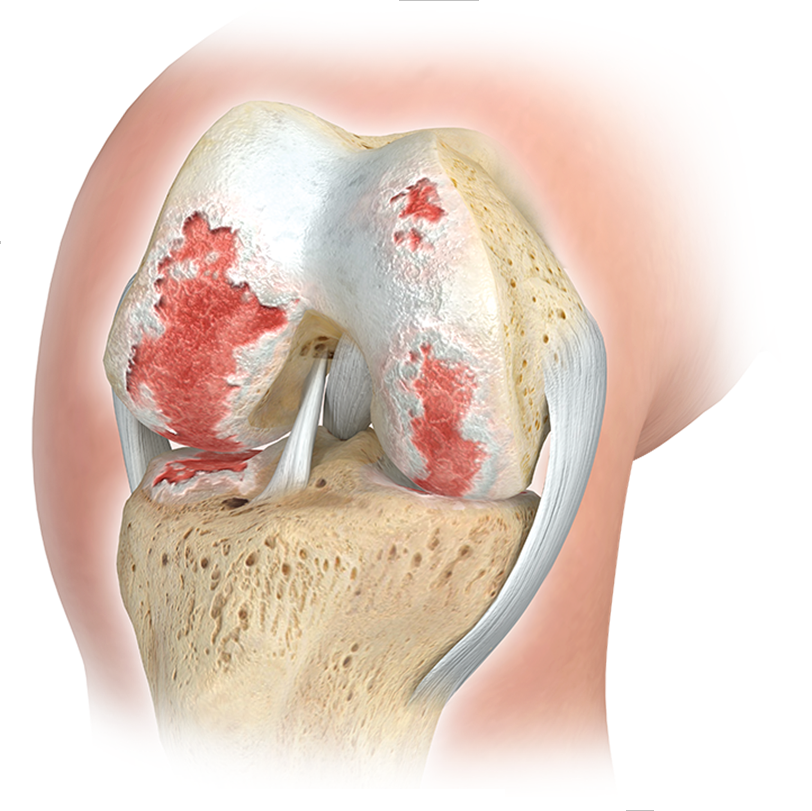

ARTHROSE KNIE

AUF GRUND der Hohen Belastungen, welchen die Kniegelenke ausgesetzt sind, kommt es hier sehr häufig im laufe des Lebens zu Verschleisserscheinungen mit zum deutlichen Beschwerden und Einschränkungen der lebensqualität. frühe sportverletzungen, fehlstellungen oder Übergewicht begünstigen diese entwicklung massgeblich.

Eine Knie-Totalendoprothese, kurz Knie-TEP, ist ein operativer Eingriff, bei dem die verschlissenen Oberflächen des Kniegelenks durch hochwertige Implantate aus Metall und Kunststoff ersetzt werden. Dieser Gelenkersatz ahmt die natürliche Funktion des Knies nach und ermöglicht wieder einen reibungslosen und schmerzarmen Bewegungsablauf. Ein solcher Eingriff wird in der Regel dann empfohlen, wenn der Gelenkknorpel durch Arthrose (Gonarthrose) so stark geschädigt ist, dass der Patient unter dauerhaften Schmerzen, Bewegungseinschränkungen und einem Verlust an Lebensqualität leidet.